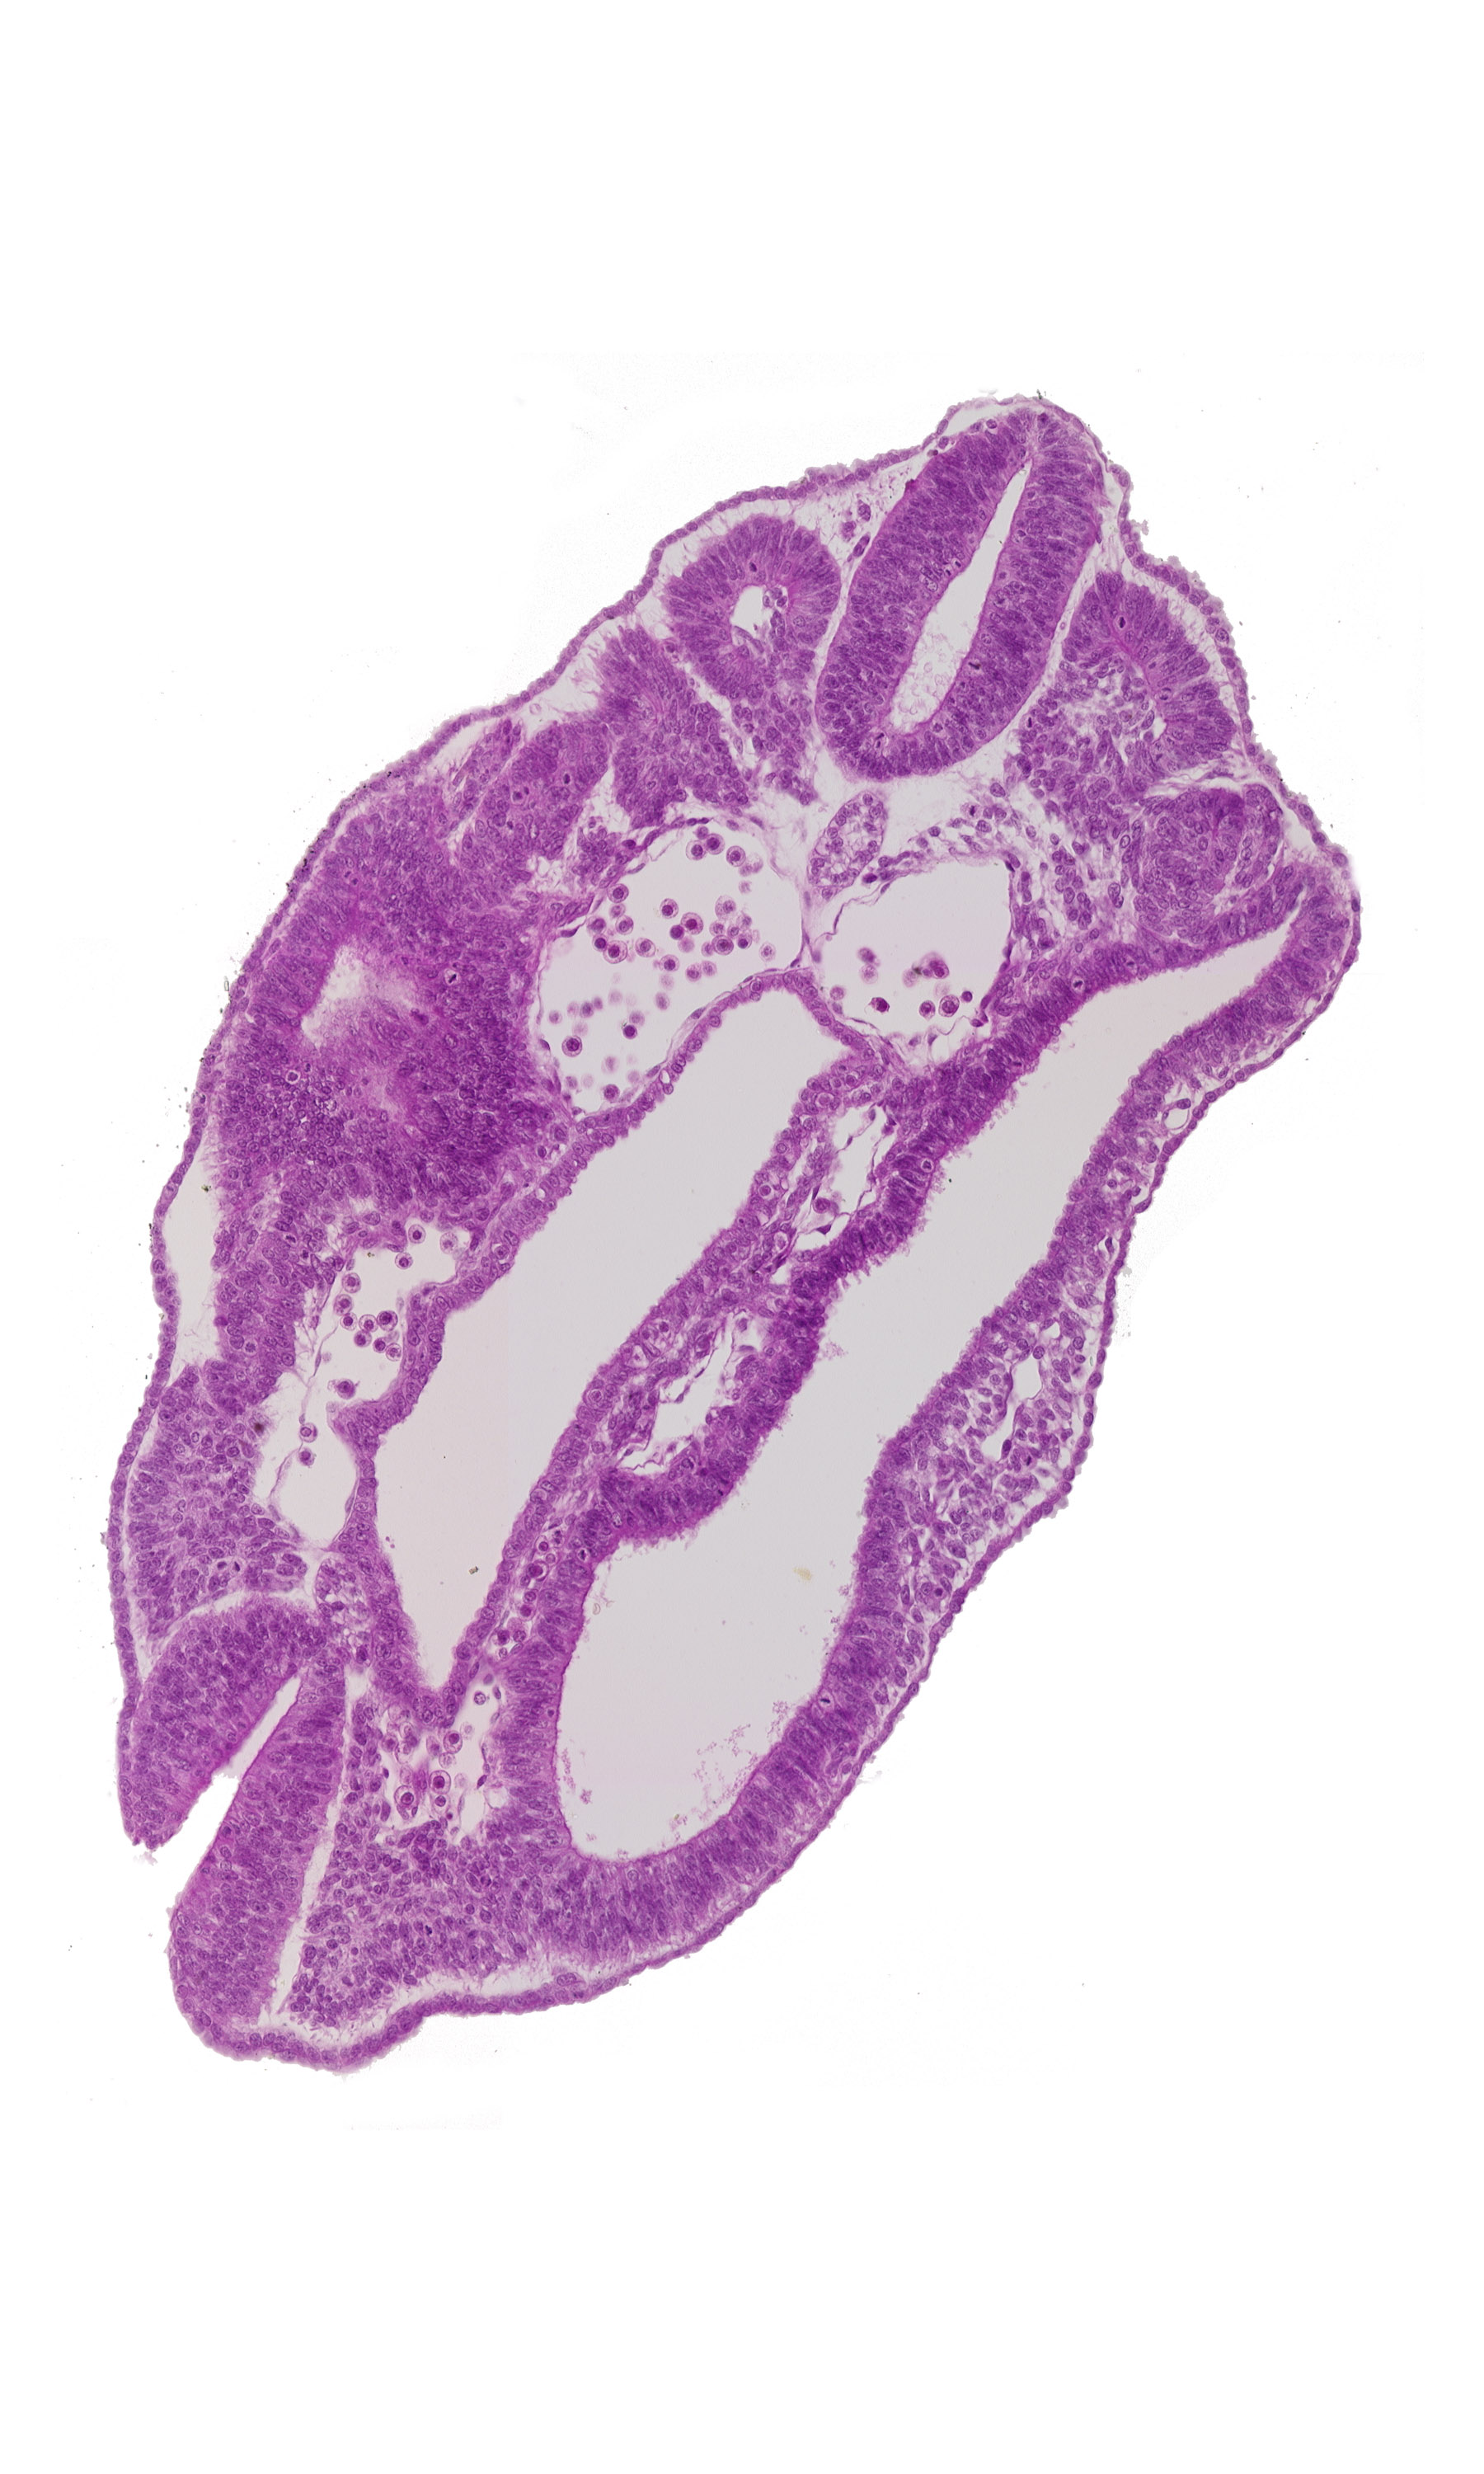

Carnegie Embryo #8943 | Location: 08-03-07

Keywords: caudal edge of peritoneal cavity, cephalic edge of caudal neuropore, dermatomyotome 16 (T-4), hindgut, peritoneal cavity, sclerotome

Source: The Virtual Human Embryo.